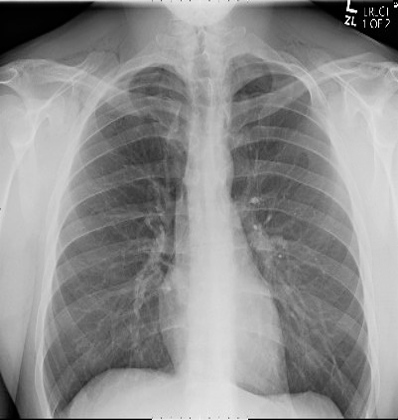

Diagnostic testing. The patient’s white cell count was 12.04 (normal range, 3.50-10.80) and his creatinine was 2.70 (normal range, 0.7-1.2). Although no alcohol was detected in his blood sample, a drug screening was positive for amphetamines and cannabinoids. His respiratory viral panel was negative, and his rapid step was positive. The oral ulcer was cultured as well. Due to his trouble swallowing, a chest x-ray was obtained (Figure 1), which showed pneumomediastinum. The patient’s chest and neck computed tomography (CT) showed moderate pneumomediastinum (Figure 2) and extensive subcutaneous emphysema within the base of the neck (Figure 3).

Fig. 1. The patient’s anteroposterior chest x-ray is shown.